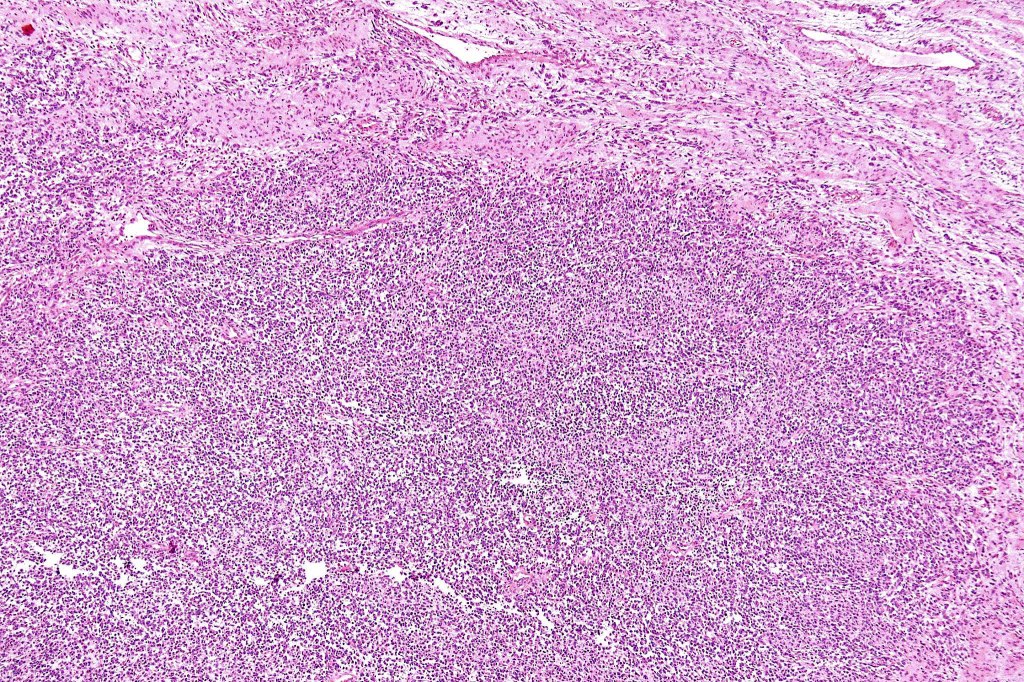

•The nodule generally merges with the adjacent nevus but sometimes it can be sharply circumscribed

•It is hypercellular and most often composed of epithelioid cells showing little pleomorphism & only occasional mitoses

•Some examples show more marked pleomorphism with prominent nucleoli and increased mitotic activity but abnormal mitoses are not a feature. These are not associated with any sinister biological potential

•Absence of necrosis, hemorrhage or Pagetoid spread in the overlying epidermis